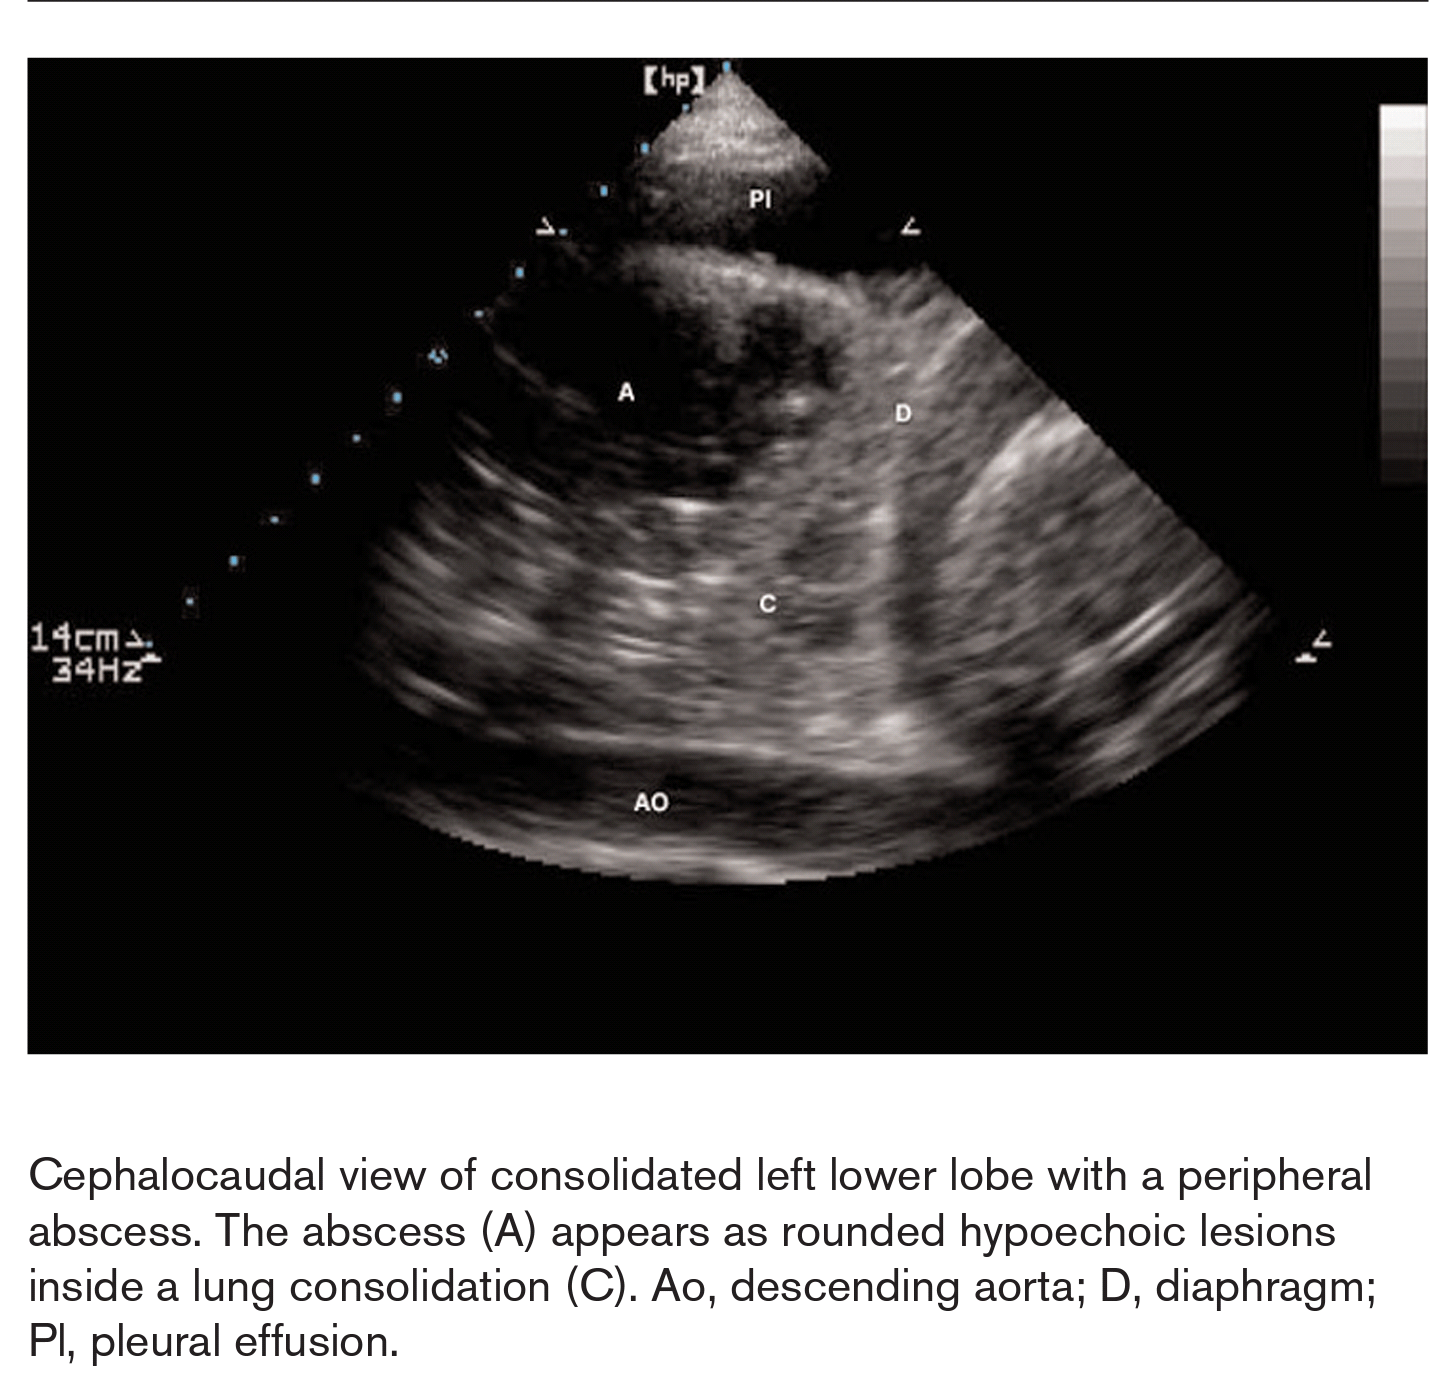

This video shows a small pleural effusion and adjacent alveolar consolidation of the lung. With each inspiration, aerated lung is interposed into the imaging window with loss of visualization of the underlying structures. This is termed the curtain sign. The 3.5 MHz transducer is in longitudinal orientation and placed perpendicular to the chest wall to scan through the 8th intercostal space in the left mid-axillary line.